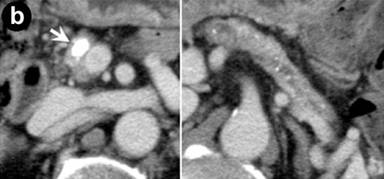

Figure 2. Images of systemic lesions after starting steroid therapy. a. Endoscopic retrograde ureterography showed a stricture at the lower portion of right ureter, 8 mm in length (arrow). b. Following computed tomography demonstrated a large stone (7x10 mm) stuck in the main pancreatic duct at pancreatic head (arrow) and many small stones distributed within the pancreatic body and tail. c. Following endoscopic retrograde pancreatography demonstrated a stone stuck in the dilated main pancreatic duct at pancreatic head (arrow) and floating stones in the upstream (small arrows). |

Nine months after starting steroid therapy with a maintenance dose of prednisolone (5 mg/day), the serum levels of IgG (1,896 mg/dL), ANA (positive at x160 dilution), and HbA1c (9.8%) were elevated, and we increased the steroid amount to 15 mg/day. At that time, CT demonstrated a pancreatic stone, 7x10 mm in size, settled in the main pancreatic duct at the pancreatic head, and scattered small stones within the atrophic pancreatic body and tail (Figure 2b). As the stones became larger, the patient began to complain of epigastria. ERP revealed a stone at the right edge of the dilated main pancreatic duct at the pancreatic head (Figure 2c). The patient was treated with extracorporeal shock wave lithotripsy (ESWL) followed by endoscopic pancreatic stent insertion. This therapy was effective, but the stone could not be completely eliminated, and the procedure was repeated four times during the following two years. Occasionally, the main pancreatic duct was severely narrowed and even insertion of the guide wire was difficult.